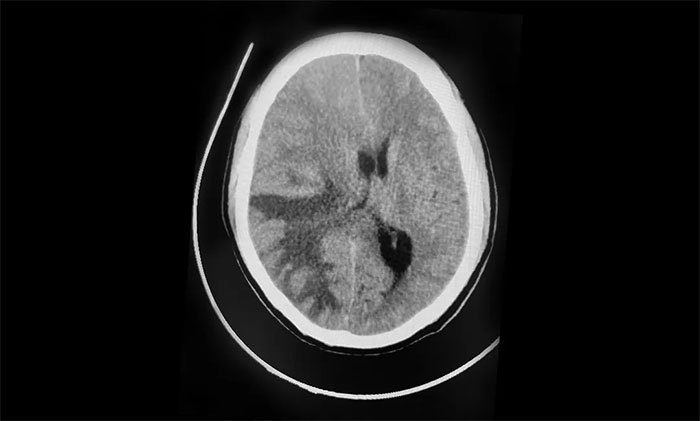

1月5日早晨,张先生反复出现头痛、呕吐。肿瘤科、放疗科、神经外科6B病区专家紧急会诊,并急查头颅CT。影像显示,右侧额顶叶、枕叶见多枚大小不等团块状等密度影,最大者约4.2*4.8cm,周围大片低密度水肿。右侧脑室受压变窄,中线结构向左侧偏移超过1.0cm。

▲ 中线结构向左侧偏移

“手术宜早不宜迟,越早越好!”潘仁龙主任、吴治群博士分析指出。结合影像表现,共发现有三处肿瘤,并伴严重水肿,脑组织向脑干处移位,脑干受压明显,颅内压急剧升高,患者意识状态逐渐恶化,已经处于脑疝临界状态。